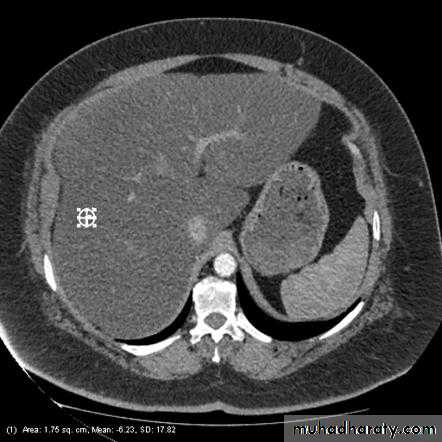

CT : IV contrast is usually given to emphasize the density between normal parenchyma and pathological lesions. The liver has dual blood supply from hepatic artery and portal vein. The liver is divided into 8 segments determined by hepatic and portal veins. The normal liver is higher or equal in density to the spleen. The normal intrahepatic bile ducts are not visible.

Fatty infiltration of the liver

It is a frequent finding, particularly in those with hypercholesterolaemia, obesity, diabetes or those who take alcohol to excess. It may involve the whole liver or it may just involve individual subsections

At CT, liver density is less than splenic density

At US, increased liver echogenicity (bright liver)MRI useful in problem cases because fat gives a characteristic set of signals